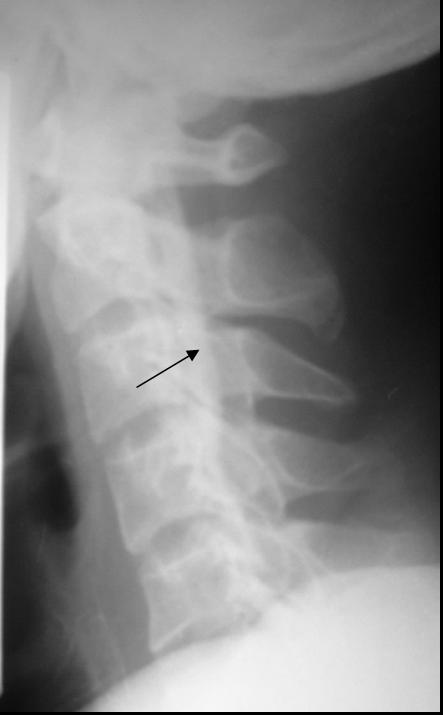

A 9-year-old male presented with mass on back since he was 4 year old. Local doctor have did operation but mass have growth again. We can see scar incision on back mass. Recently, he developed leg weekness now he cant walk.